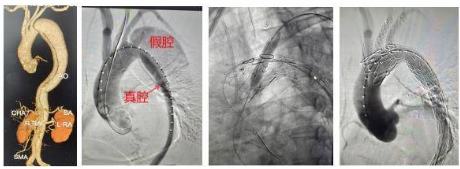

因此,瑞康医院心内科团队决定通过主动脉支架体外开窗方法保住左锁骨下和左颈总动脉,根据术中测量结果和3D打印模型,选择主动脉覆膜支架体外开窗,取左颈总动脉及左锁骨下动脉开窗并缝内分支支架一枚,同时行支架束径。其间,自右股动脉入路送入主动脉支架至弓部预定位置半释放,分别经左颈总动脉及左肱动脉入路,导丝配合导管超选开窗洞口至主动脉支架内,沿导丝送入两枚分支支架,分别释放主动脉及分支支架。术后,造影显示各分支动脉畅通,夹层完全消失无内漏。手术完美结束。

主动脉夹层是一种极其危险的心血管急症,主要表现为突发性剧烈胸背痛。这种疾病就像轮胎内胎破了个口子,血液从血管最内层(内膜)的破口冲进血管壁中间层,像吹气球一样把血管壁撑开形成血肿,随着血液不断冲击,血管壁的内层和中层被撕裂分离。此时,血管被撕开形成真假两个通道,即真腔和假腔,两者之间被撕裂的血管壁(内膜片)隔开。